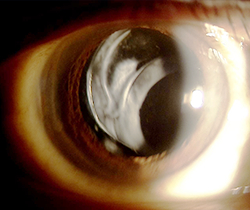

인공수정체의 위치 이상(인공수정체 탈구)

백내장 수술시 삽입했던 인공수정체가 정상 위치를 벗아난 경우를 말하며, 이탈된 정도에 따라 앞이 뿌옇게 보이고, 시력저하가 나타납니다.

야마네 고정술

수술 전

수술 후